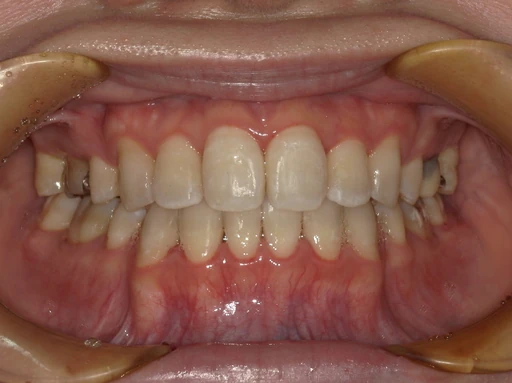

症例1

治療前は歯の重なりやガタつきが気になる状態でしたが、インビザライン治療により、歯列が整い、口元の印象が大きく改善しました。

金属の装置を使用しないため、治療中も自然な見た目を保てる点が、インビザラインの大きなメリットです。

「矯正していることを周囲に気づかれたくない」という方にも選ばれています。